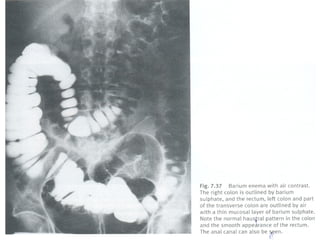

 Radiologia simples e com cantrast-barium